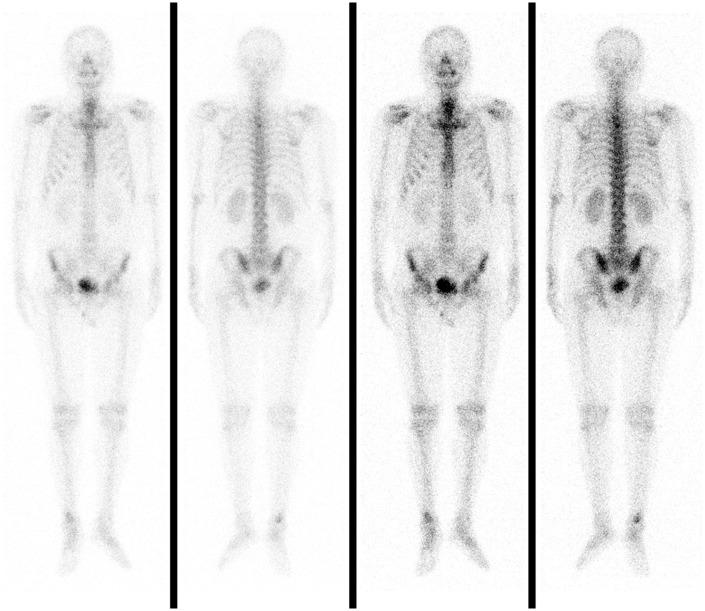

Rosai-Dorfman disease (RDD) or sinus histiocytosis with massive lymphadenopathy is a rare benign disorder usually characterized by massive painless cervical lymphadenopathy and systemic manifestations. Extranodal involvement, especially spinal involvement, is extremely rare. We report a 41-year-old man who presented with only intermittent dorsodynia. His condition was diagnosed as non-specific inflammatory disease on the basis of preoperative puncture biopsy results. We performed total surgical resection. Histopathological findings showed distinctive emperipolesis and immunohistochemistry results were positive for cluster of differentiation CD68 and S100 and negative for CD1a. A good prognosis was confirmed at the 3-month follow-up visit. This is the first case of RDD of the subdural spine with such a long segment lesion. There is still no consensus regarding appropriate therapy for this type of RDD and the preoperative diagnosis remains challenging. The unusual presentation of our case serves as a reference when diagnosing and treating RDD.

罗萨伊-多夫曼病(RDD)或伴有巨大淋巴结病的窦性组织细胞增生症是一种罕见的良性疾病,通常表现为无痛性巨大颈部淋巴结病和全身症状。结外受累,尤其是脊柱受累极为罕见。我们报告一名41岁男性,仅表现为间歇性背痛。根据术前穿刺活检结果,其病情被诊断为非特异性炎症性疾病。我们进行了全手术切除。组织病理学检查结果显示有独特的血细胞吞噬现象,免疫组化结果显示分化簇CD68和S100呈阳性,CD1a呈阴性。在3个月的随访中证实预后良好。这是首例硬膜下脊柱RDD伴如此长节段病变的病例。对于这类RDD的适当治疗仍未达成共识,术前诊断仍然具有挑战性。我们病例的不寻常表现为RDD的诊断和治疗提供了参考。